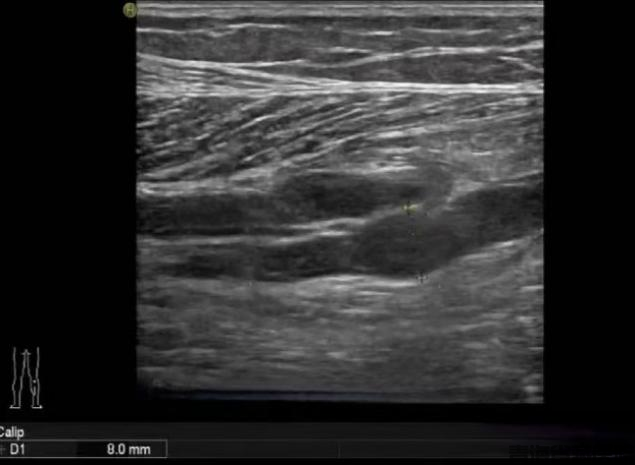

2)超声检查(准确率98%)表现:血管鼓胀变形呈"腊肠样"血流信号突然"消失"探头按压血管无法完全压扁

图片3.png

常规二维灰阶超声检查

小腿肌间静脉管腔扩张,充满低回声,探头加压无法压扁,提示血栓形成